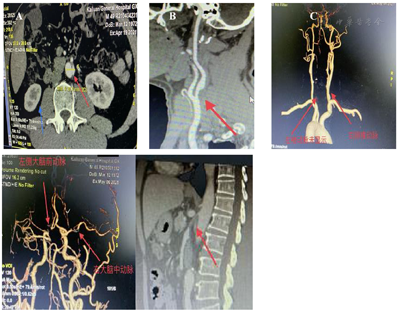

行全主动脉血管强化CT提示:腹主动脉透壁溃疡、左肾动脉支架内狭窄,左侧椎动脉、左侧大脑前动脉A1段闭塞,右侧大脑中动脉M1段重度狭窄,肠系膜上动脉开口重度狭窄。

全主动脉血管造影:腹主动脉透壁溃疡,右肾缩小。左侧颈内起始部狭窄、左侧椎动脉闭塞、左侧大脑前动脉A1段闭塞,右侧大脑中动脉M1段重度狭窄,肠系膜上动脉狭窄开口重度狭窄(图2)。